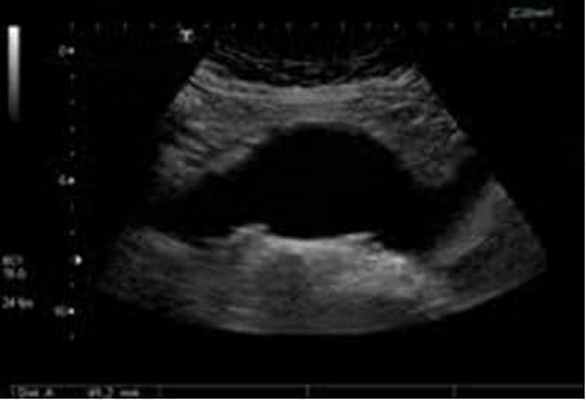

- Ультразвуковое исследование (УЗИ);

Ультразвуковое дуплексное исследование – "золотой стандарт" скринингового обследования пациентов (обнаружение и динамическое наблюдение);

Чтобы диагностировать аневризму брюшной аорты необходимо пройти ультразвуковое исследование (УЗИ) — дуплексное или триплексное сканирование брюшной аорты.